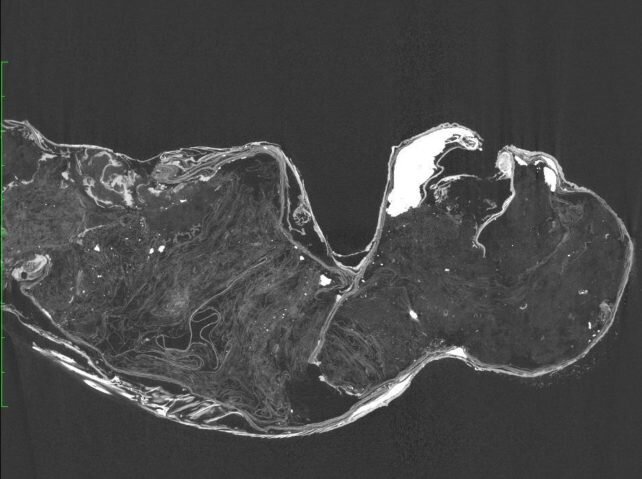

برای درک ماهیت دست کم یکی از این نینگیوهای مومیاییشده، تیم تحقیقاتی با معب همکاری کرد تا بدون اینکه آسیبی به نمونه برسد، آن را به طور کامل و دقیق مشاهده کند. برای این کار به غیر از ارزیابی بصری، از تصویربرداری با اشعه ایکس، تصویربرداری سیتی، میکروسکوپ نوری و الکترونی، آنالیز اشعه فلورسنت، آنالیز DNA و تاریخگذاری رادیوکربن استفاده شد.

در این تحقیق مشاهده شد که به غیر از فک پایین، نینگیو کاملا فاقد معماری اسکلتی است و بنابراین، این مومیایی حتی مثل پری دریایی تقلبی فیجی، مخلوق فرانکنشتاینی حاصل دوختن نیمی میمون و نیمی ماهی هم نیست.

اسکنها نشان داد که این شیء ترکیب درهم و برهمی از چیزها است. برای ساخت آن از چوب استفاده نشده، اما در عوض عمدتا پارچه، پنبه و کاغذ در ساخت بافت آن به کار رفته و با مادهای که از مخلوط خمیریشکل پودر زغال چوب و شن و ماسه درست شده، پوشانده شده است. قسمت سر عمدتا از جنس پنبه است و مادهای گچمانند روی آن مالیده شده است.

موی سرش، موی حیوان است و فلس آن از دو نوع ماهی گرفته شده است. برای قسمت فوقانی بدن از پوست ماهی پفدار استفاده شده و برای قسمت پایینی بدن از پوست فلسدار گونهای از اردکماهی به کار رفته است. ناخنهای پنج انگشت از جنس کراتین حیوانی است که احتمالا نوعی شاخ است و استخوان فک هم متعلق به نوعی ماهی گوشتخوار است.

محققان در پایان میگویند: بدن این «پریدریایی مومیاییشده» با پوست یک جور ماهی پوشیده شده است و قسمت بالایی بدن از پارچه و کاغذ ساخته شده است. این از کاغذ چند لایه و پوست ماهی پف کرده، با پنبه و سایر مواد پرکننده و مادهای گچ مانند به عنوان پایه ساخته شده و گمان میرود متعلق به اواخر دهه ۱۸۰۰ باشد.»